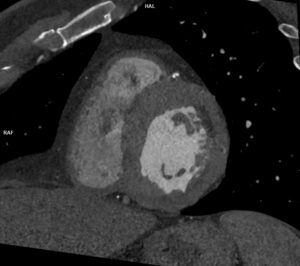

Figura 2: reconstrucție VRT din angioCT arterial cu stenoză de trunchi celiac la origine și dilatație poststenotică

Discuţie caz nr 126: Investigația CT a fost realizată pentru control postoperator la un pacient cu proteză de aorta ascendentă pentru disecție de aorta Stanford tip A operată. Se evidențiază proteză de aortă ascendentă în poziție normală, fără dezvoltări anevrismale la nivelul anastomozelor precum și disecție de aorta toracică și abdominală restantă cu orificii de intrare proximal precum și distal în vecinătatea originii arterei renale drepte, iar faldul de disecție nu evoluează la nivelul ramurilor. În plus, se evidențiază stenoză proximală de trunchi celiac cu dilatație poststenotică